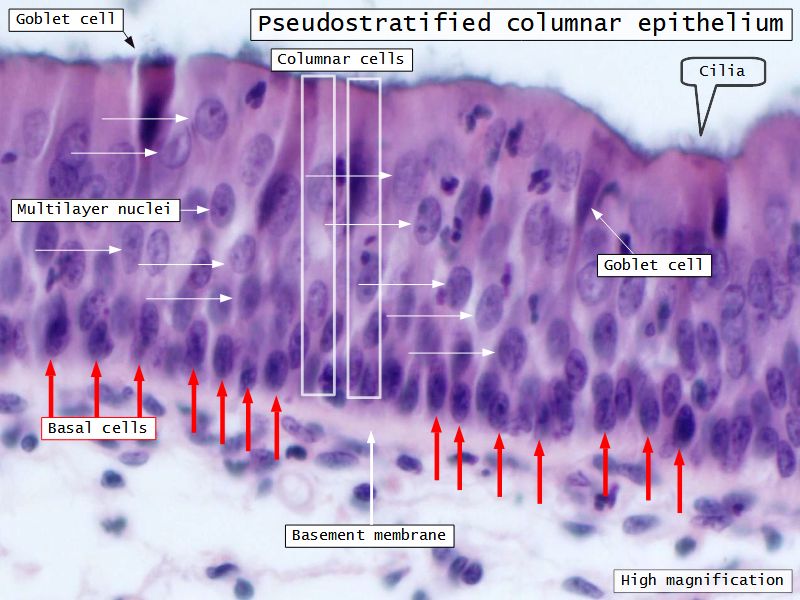

Respiratory epithelium

- Pseudostratified

- Ciliated

- Columnar

- Epithelium with

- 4 Cells

- Ciliated columnar cells

- Non-ciliated columnar cells

- Goblet cells

- Basal cells